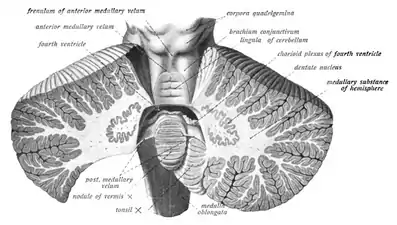

Sección sagital del tronco cerebral. Sección coronal del cerebelo.

Sección coronal del cerebelo. Arbor vitae y pedúnculos cerebelosos.

Arbor vitae y pedúnculos cerebelosos.